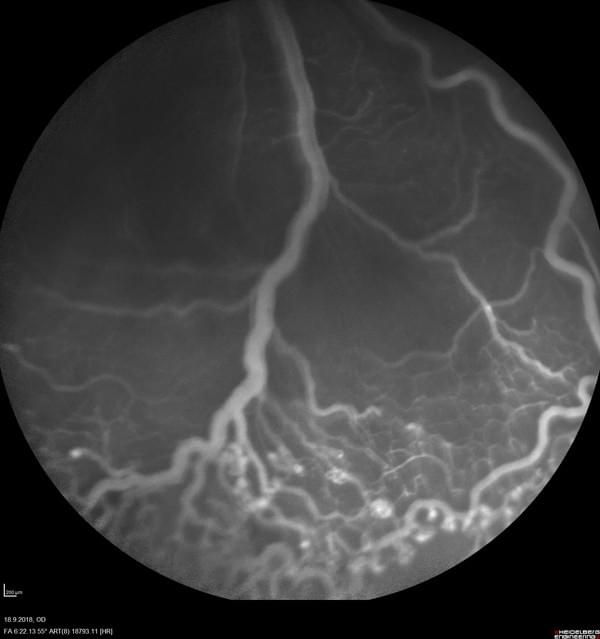

酸素誘発性網膜症(OIR)モデルを用い、抗VEGF薬Afliberceptの有効性を検証した前臨床試験です。高酸素環境と常酸素環境を交互に与え、血管閉塞と再灌流による病的新生血管を再現。投与群では新生血管面積が顕著に減少し、血管構造の正常化が確認されました。この結果はEVER 2018で発表され、同社の画像解析技術と血管定量評価手法が抗血管新生薬の開発支援に有用であることをアピールしました。

酸素濃度を制御して網膜血管の閉塞と再灌流を引き起こし、新生血管の形成を再現するモデルです。抗VEGF薬など血管新生阻害薬の有効性評価に広く利用され、血管構造を画像解析で定量化できます。